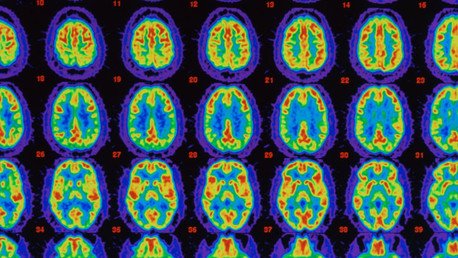

El doctor Doug Brown explicó durante la conferencia cómo el medicamento reduce las placas de proteína beta-amiloide que se acumulan en el cerebro, retardando el proceso degenerativo de la enfermedad.